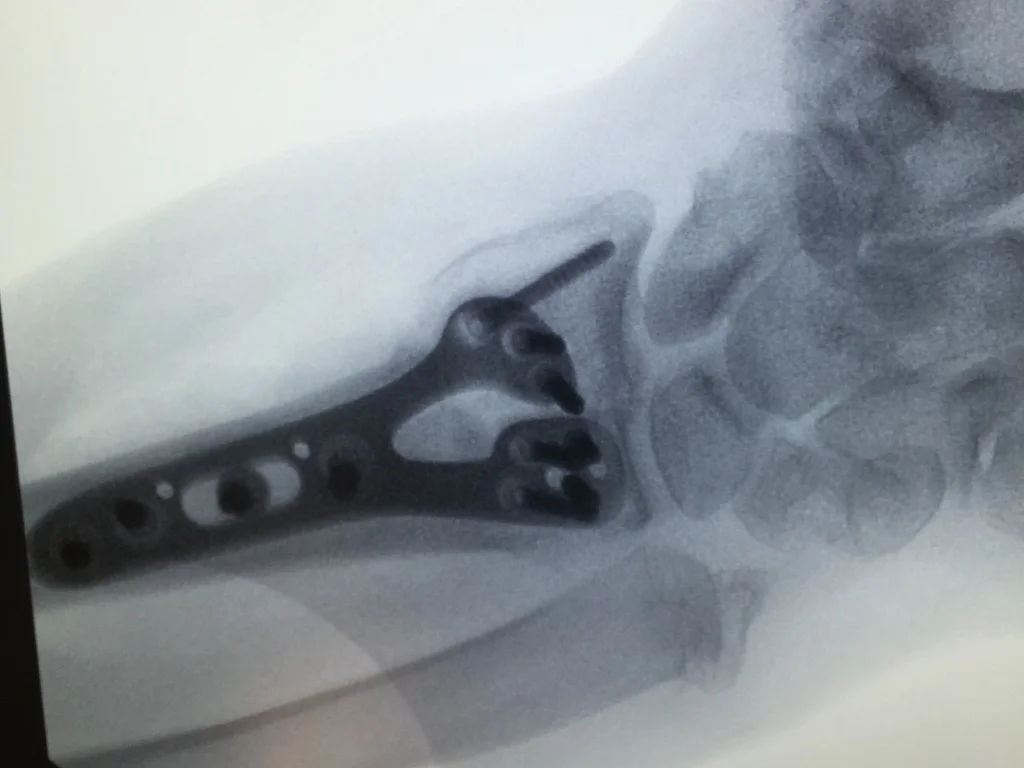

Distal Radius fractures are among the most common fractures or breaks of the human skeleton.  Nearly all wrist fractures or broken wrists are distal radius fractures.  Many of these injuries can be treated non operatively in a cast or brace, but usually require 8 weeks of immobilization.  In patients with displaced fractures or breaks that go into the joint (intraarticular fractures), surgery is often recommended and offers a faster rehabilitation potential.  Cast immobilization is often only 3 weeks or less in patients who have surgery.

Dr. Gray received extensive training in surgical treatment of these injuries at Mayo Clinic during his fellowship, including fragment-specific fixation.  While on the faculty at University of Miami, he treated numerous high-energy fractures and worked with Jorge Orbay, MD the surgeon who pioneered both the surgical approach (extended FCR approach) and the implants (volar locking plates) that are currently the standard of care throughout the world. Dr. Gray is a high-volume surgeon performing 50-100 wrist fracture repairs yearly and 800 total surgeries each year.